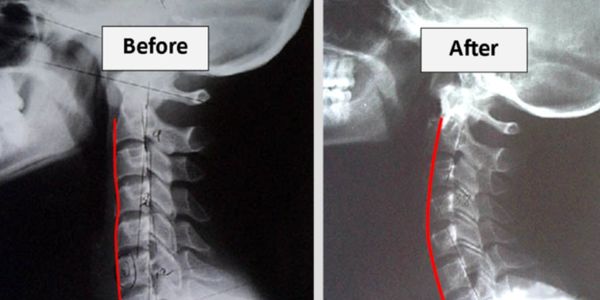

Proper, or normal, posture is a matter of simple engineering. The human body is designed with the head, rib cage, and pelvis perfectly centered and balanced on each other. From the front, the spine is perfectly aligned with gravity. But the spine, when viewed from the side, contains three curves to properly balance the weight of your body and allow free movement. A CBP treatment plan at Roybal Chiropractic has corrective exercises, adjustments, and traction. Please read below for a description of each of these services.

Traction uses weights and other tools to treat muscular and skeletal disorders. Those disorders can include: injuries to the joints, muscles, vertebrae and ligaments pinched or compressed nerves. The way traction can help is by stretching the ligaments and muscles which increases the space between your vertebrae. Traction can also help relieve your pain which can be caused by disc degenerative disorders or by bulging or herniated discs.